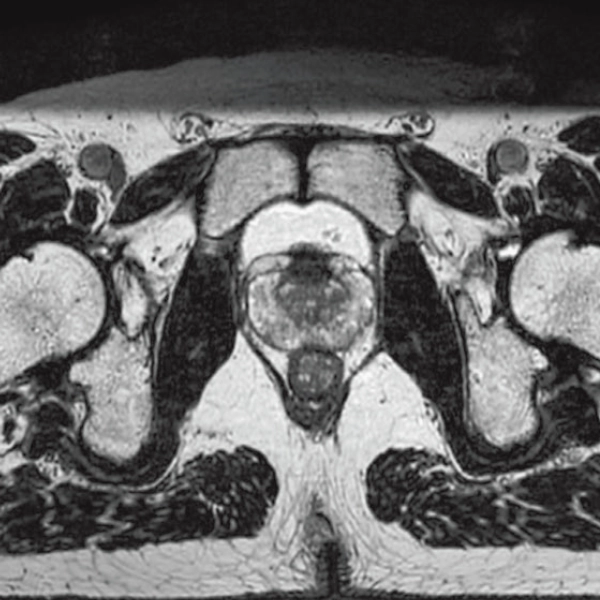

T2WI, 0.56×0.70×3.0mm, 2:28

T2*WI Multi Echo,

0.38×0.38×2.0mm